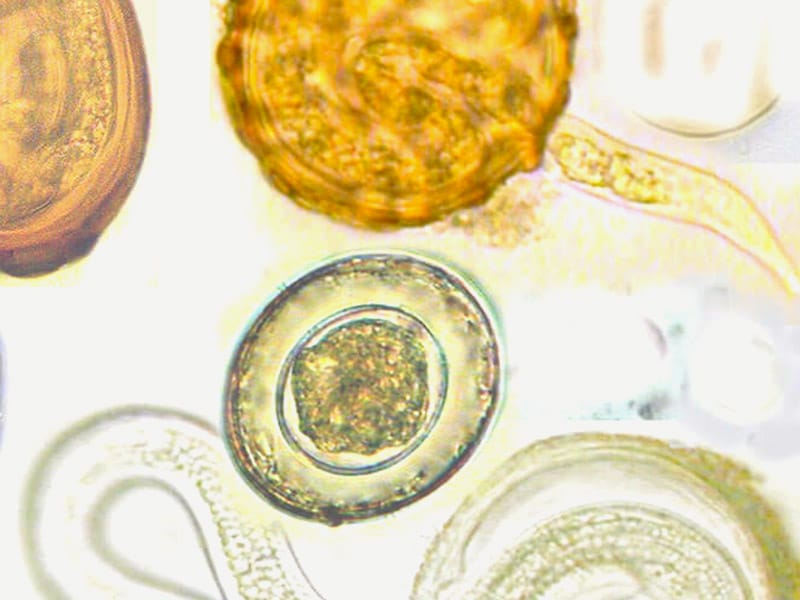

Анализ на яйца гельминтов, как следует из названия, позволяет выявить в стуле продукты жизнедеятельности червей — личинки и яйца.

Иногда могут быть обнаружены и взрослые особи, которые не всегда заметны невооружённым глазом (например, это касается небольших червей, таких как аскариды). Исследование проводится визуально, лаборанты анализируют образец под микроскопом, выявляя признаки заражения.